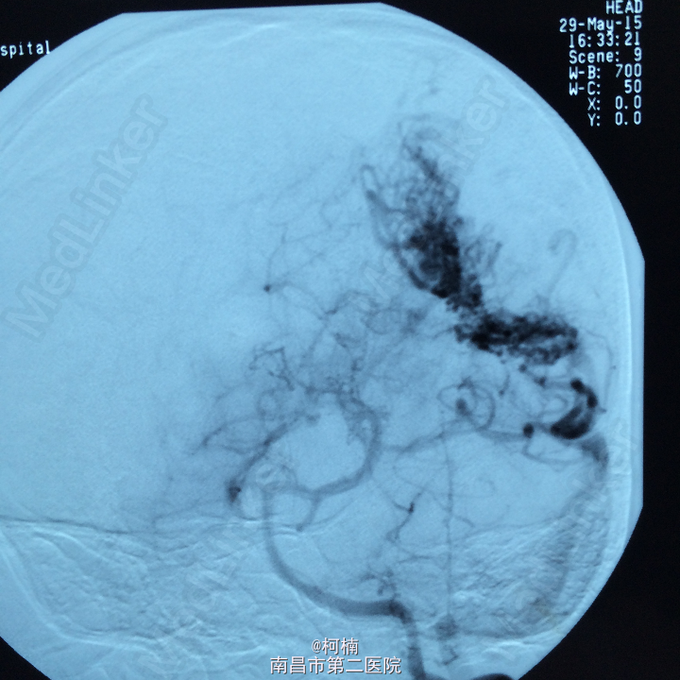

主诉:头痛伴呕吐2天,意识障碍1天 病史:患者于2天前运动后出现头晕头痛,为爆炸样头痛,程度较重,伴呕吐多次,呕吐物均为为内容物,伴四肢乏力,予休息处理。次日清晨患者出现头痛加重,伴呕吐,甚至模糊,呈嗜睡状态,呼之能应,遂急诊送入当地ICU治疗,查头部CT示:蛛网膜下腔出血,予脱水、止血对症治疗后患者症状无明显缓解。转入我院进一步治疗。

查体:神志朦胧,颈抵抗,右侧肢体及躯干深感觉减退,左侧正常。 辅助检查:复查CT提示左侧额叶出血破入脑室系统

诊断:脑动静脉畸形 处理:予急诊行DSA检查,提示脑动静脉畸形,予行血管内栓栓塞治疗